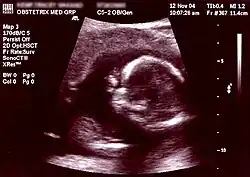

Ultrasound[8] Periodically Non-invasive/Invasive Abdominal or Transvaginal ~1 day – ~1 week Fetal development, neural tube defects, birth defects, and various other physical abnormalities (see below for specific ultrasound tests) NA

Ultrasonography is an example of a non-invasive diagnostic prenatal test.

Non-invasive Ultrasound detection Commonly dating scans (sometimes known as booking scans or dating ultrasounds) from 7 weeks to confirm pregnancy dates and look for multiple pregnancies. The specialised nuchal scan at 11–13 weeks may be used to identify higher risks of Downs syndrome. Later morphology scans, also called anatomy ultrasound, from 18 weeks may check for any abnormal development. Additional ultrasounds may be performed if there are any other problems with the pregnancy, or if the pregnancy is post-due. First or second trimester